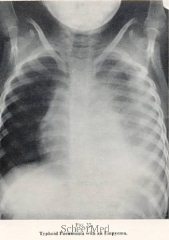

The symptoms of bronchitis can also lead to other respiratory problems such as sinusitis, asthma and complicated pneumonia.

Although bronchitis is a common respiratory disease, it is also often misdiagnosed. Because of this, Para clinical and physical examinations must be conducted in order to establish the accurate diagnoses.

With the help of the laboratory analysis and pulmonary tests, the most vital signs of bronchitis become eminent.